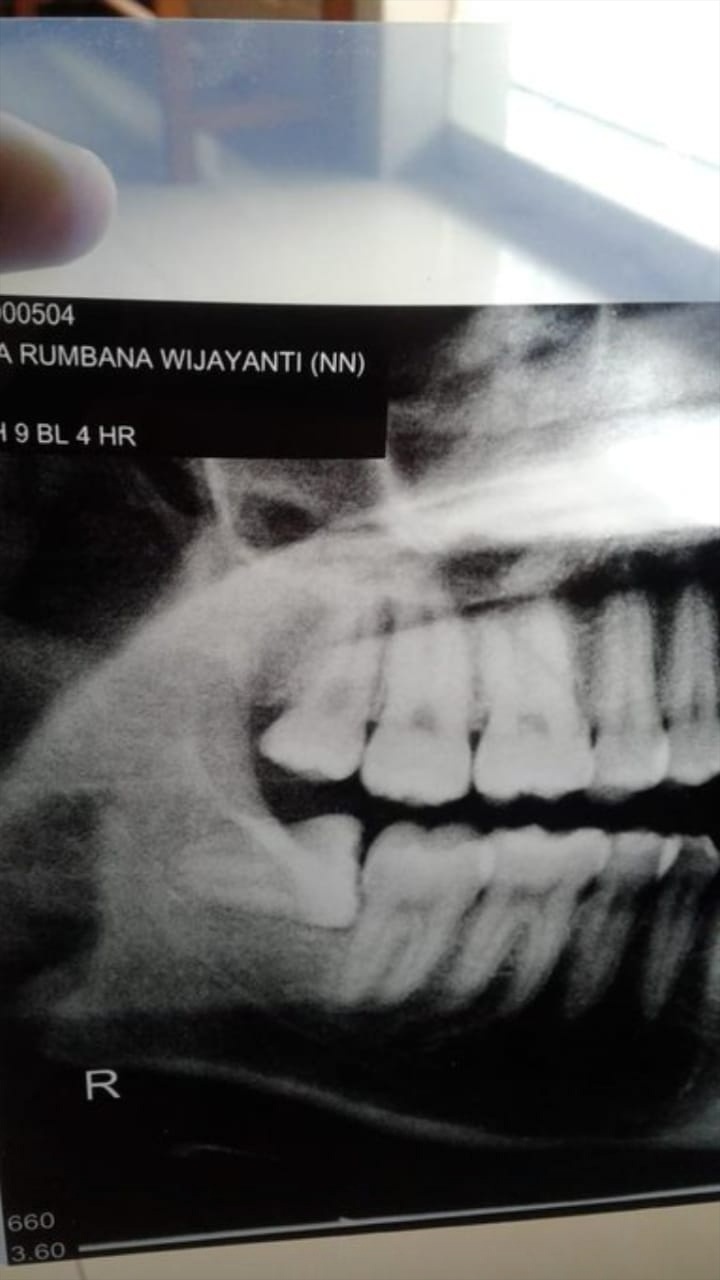

Biaya Operasi Gigi Bungsu / Minimalkan Biaya Operasi Gigi Bungsu Dengan Asuransi Gigi / Sebelum operasi, beberapa hari sebelumnya diharuskan mengambil foto rontgen gigi panoramic.

Bertujuan untuk mengganti akar gigi dan gigi yang hilang dengan akar gigi buatan (implan) yang ditanam ke dalam gusi. Untuk info lebih lanjut dan reservasi, silahkan hubungi resepsionis cabang yang ingin dituju. Dengan gigi anda bisa menggoyah berbagai makanan sebelum nantinya lanjut dengan menelannya dan masuk ke dalam perut. Harga tersebut berbeda dengan tindakan operasi gigi bungsu … Sebelum operasi, beberapa hari sebelumnya diharuskan mengambil foto rontgen gigi panoramic.